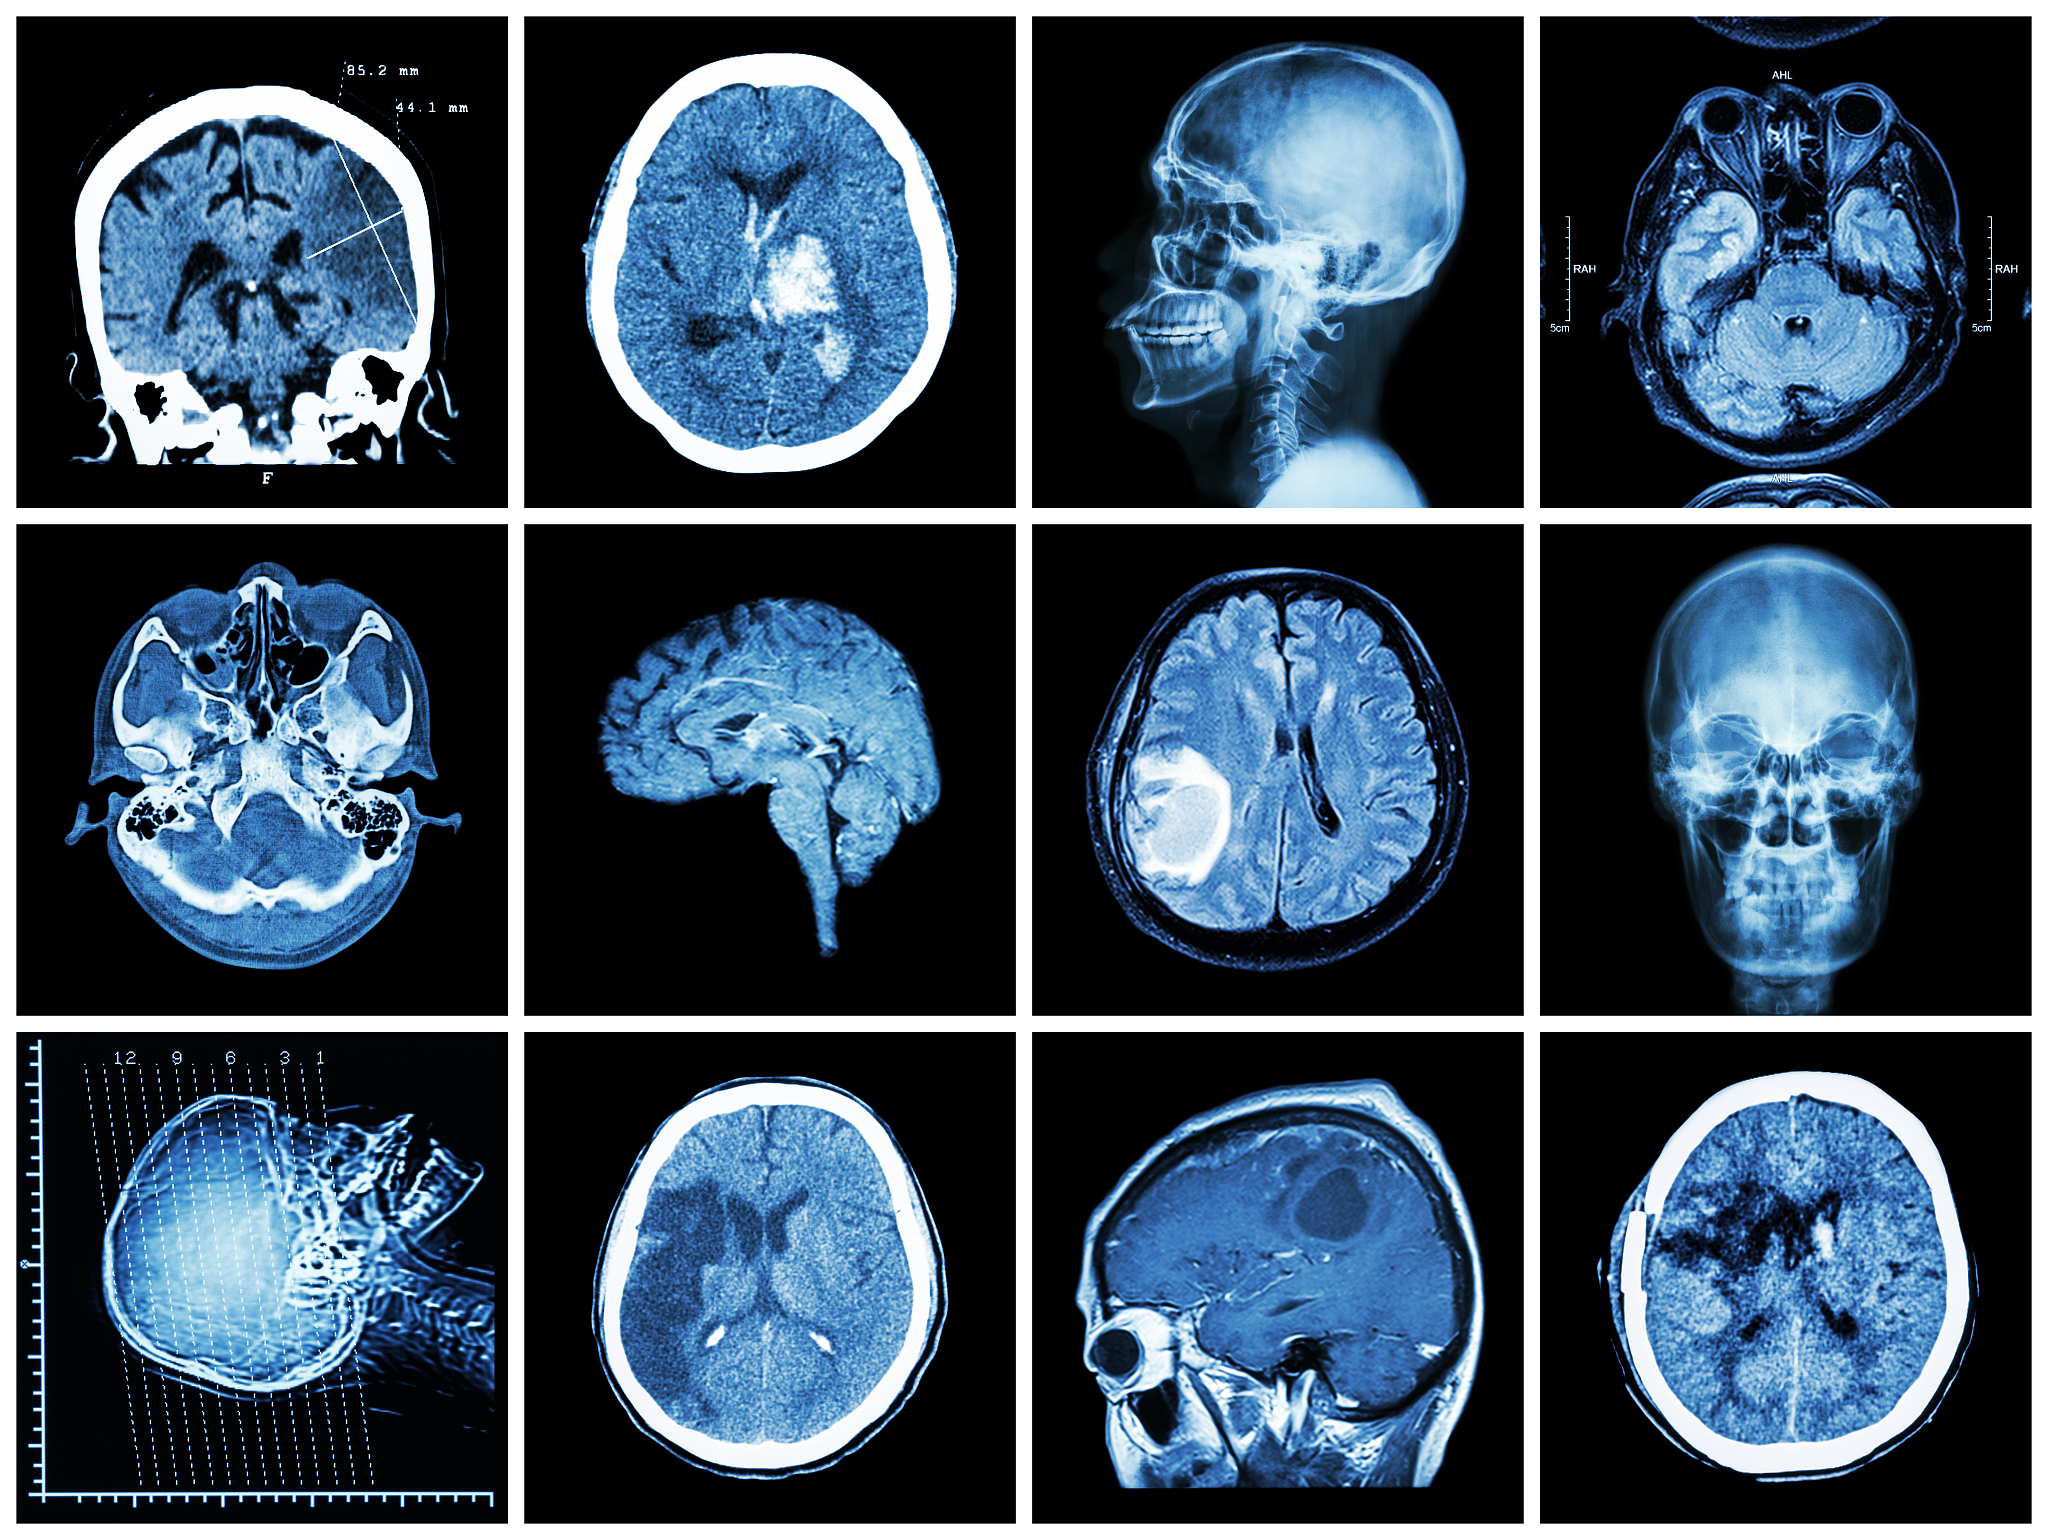

脑CT声音很大大脑受到刺激会影响拍摄吗?

脑CT扫描的声音确实很大,但通常不会对大脑产生影响。这是因为脑CT扫描使用的是X射线,而不是声波。X射线可以穿透身体组织,从而产生图像。虽然扫描过程中会发出很大的噪音,但这些声音并不会对大脑产生直接的影响。然而,对于某些人来说,这些噪音可能会引起焦虑或不适感。在这种情况下,医生可以建议患者在扫描前服用镇静剂或使用耳塞来减轻不适。

脑CT扫描的声音确实很大,但通常不会对大脑产生影响。这是因为脑CT扫描使用的是X射线,而不是声波。X射线可以穿透身体组织,从而产生图像。虽然扫描过程中会发出很大的噪音,但这些声音并不会对大脑产生直接的影响。然而,对于某些人来说,这些噪音可能会引起焦虑或不适感。在这种情况下,医生可以建议患者在扫描前服用镇静剂或使用耳塞来减轻不适。